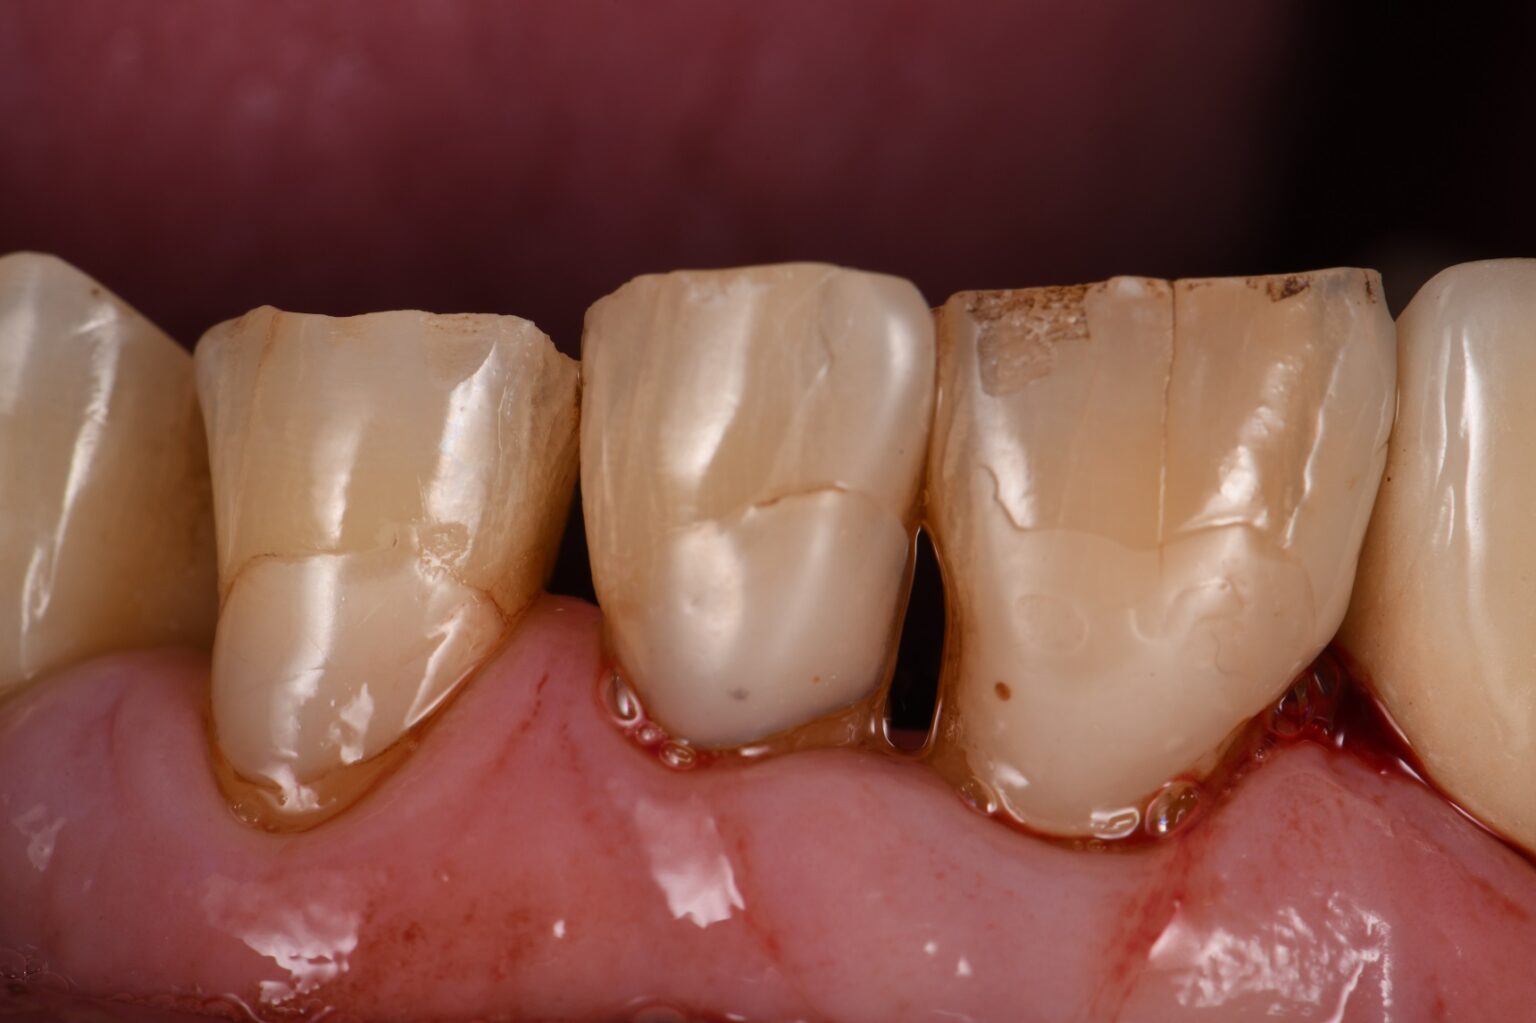

Large direct restorations on abrasion lesions Large direct restorations What Is Denture Abrasion this condition, called dental abrasion, can occur when any foreign object causes friction against your teeth and gradually wears away the enamel on the surface. what is dental abrasion? dental abrasion refers to the wearing away of tooth enamel, which is the hard outer layer of the tooth. when dental abrasion appears, it means your enamel. What Is Denture Abrasion.

Extreme root abrasion restorations What Is Denture Abrasion It can occur due to various factors, such as aggressive tooth brushing, abrasive toothpaste, bruxism (teeth grinding), and diet Some dentures replace a few missing teeth. a dental abrasion is a loss of tooth structure that occurs when the tooth is cleaned with a toothbrush or other cleaning device. when dental abrasion appears, it means your enamel has. What Is Denture Abrasion.